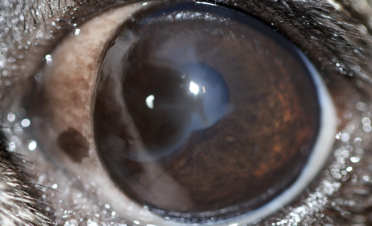

La queratitis pigmentaria se caracteriza por la aparición de melanina (el pigmento encargado de dar color a los ojos y la piel) en la superficie ocular, de forma que puede llegar a cubrirla totalmente, provocando pérdida de visión.

Suele darse como resultado de una irritación o de una inflamación crónica de la córnea, que es la capa transparente de la superficie del ojo que protege estructuras oculares como el iris y el cristalino.

Normalmente la queratitis pigmentaria afecta a los dos ojos de un Carlino o Pug. El ojo seco es un factor que predispone a esta patología, pero también puede darse en casos donde no hay sequedad ocular. Se da normalmente por irritación corneal crónica por el entropión, sequedad ocular, triquiasis o lagoftalmía, pero se cree que algunos carlinos lo desarrollan con origen genético. La forma de los párpados juega también un papel importante en el desarrollo de este problema. En algunos casos puede llegar a provocar severa pérdida de visión.